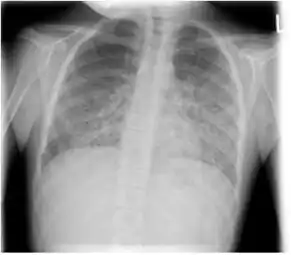

The diagnosis can be confirmed by the characteristic appearance of the chest X-ray and an arterial oxygen level that is strikingly lower than would be expected from symptoms. Gallium 67 scans are also useful in the diagnosis. They are abnormal in a high percent of cases and are often positive before the chest X-ray becomes abnormal. Chest X-ray typically shows widespread pulmonary infiltrates. CT scan may show pulmonary cysts[20] [2][21].

Tuberculosis radiographic image